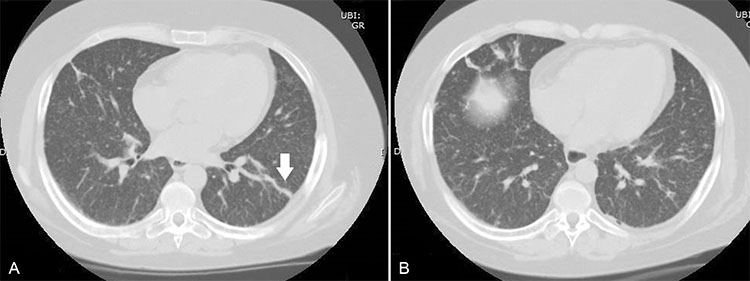

Mujer con antecedentes de lupus eritematoso sistémico en tratamiento con inmunosupresores, hospitalizada por sospecha de neumonía. Se realiza TC de tórax donde destacan: (a y b) múltiples micronódulos de distribución difusa en parénquima pulmonar. También se visualizaron algunos nódulos bilaterales, de bordes mal definidos. (a) Se visualizaron algunas imágenes lineales hiperdensas de aspecto cicatricial (flecha), que comprometen principalmente las bases pulmonares en sus porciones periféricas.

Generalmente el compromiso por TBC miliar, se resuelve con tratamiento sin dejar cicatrices o calcificaciones.